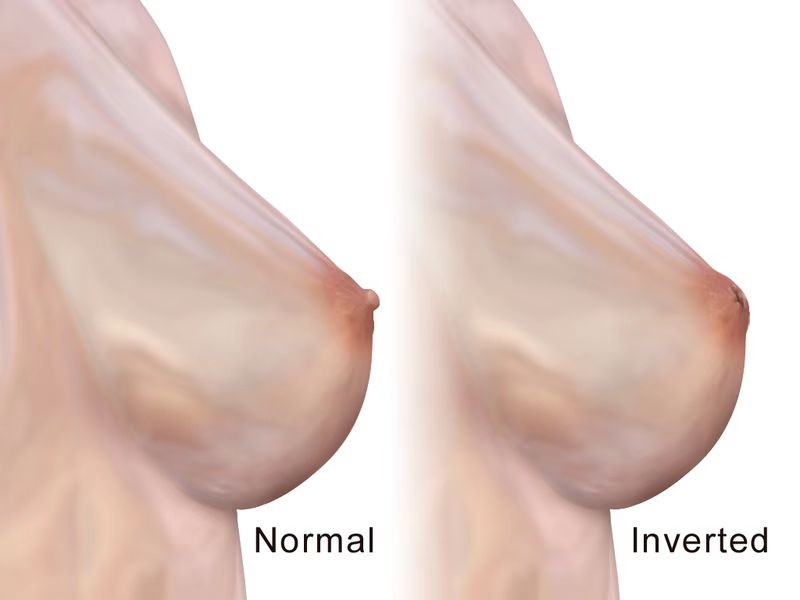

怎麼才算乳頭內陷

什麼叫乳頭內陷